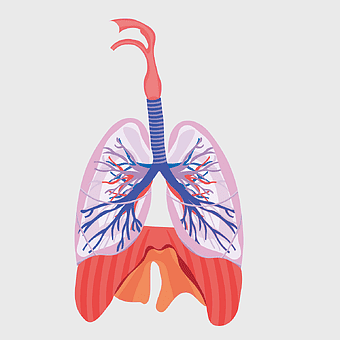

1200x1200px

lung anatomy, respiratory system illustration, pulmonary alveoli structure, trachea and bronchi, human lung function, diaphragm movement, breathing process diagram -